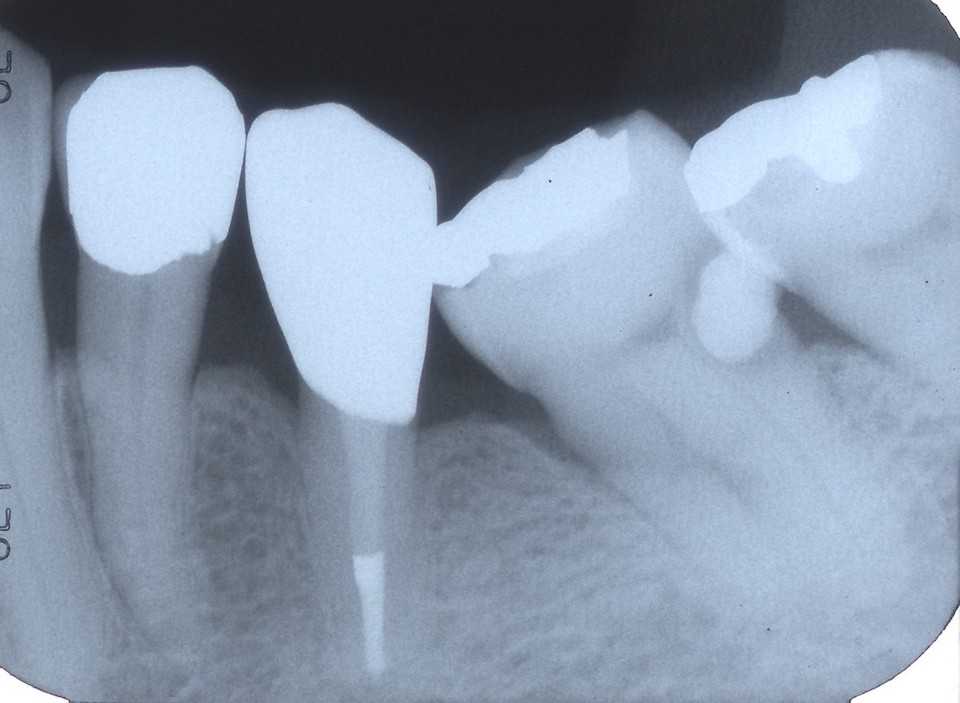

これがその歯医者さんでのレントゲン写真でデジタルなので陰影が強調されてひどい虫歯のように見える。